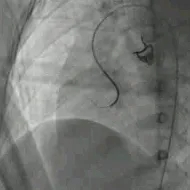

建立输送轨道

建立股动脉-VSD-股静脉轨道,沿泥鳅导丝送7F输送鞘至左室,选择6mm对称型、腰高7mm全降解封堵器。

左右盘面展开并锁定

左侧伞盘出鞘为球状,牵拉成型线后形态佳,后展开右盘,封堵器呈现“长哑铃状”,主动脉瓣少量反流。

轻轻牵拉成型线使封堵器成型,牵拉后左伞盘被拉进瘤腔内。

左右盘展开后,封堵器未锁定时造影可见封堵器中间少量反流,主动脉瓣少量反流。